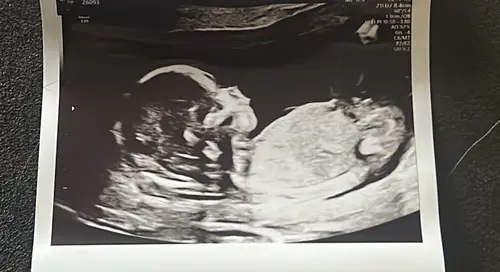

Is dit duidelijke een meisje? Door de nub dachten we namelijk eerst een jongen